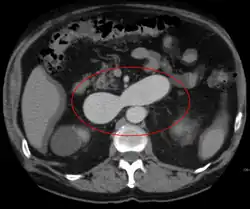

An arterial venous malformation of the left kidney and a simple cyst of the right kidney

An arterial venous malformation of the left kidney leading to aneurysmal dilatation of the left renal vein and inferior vena cava